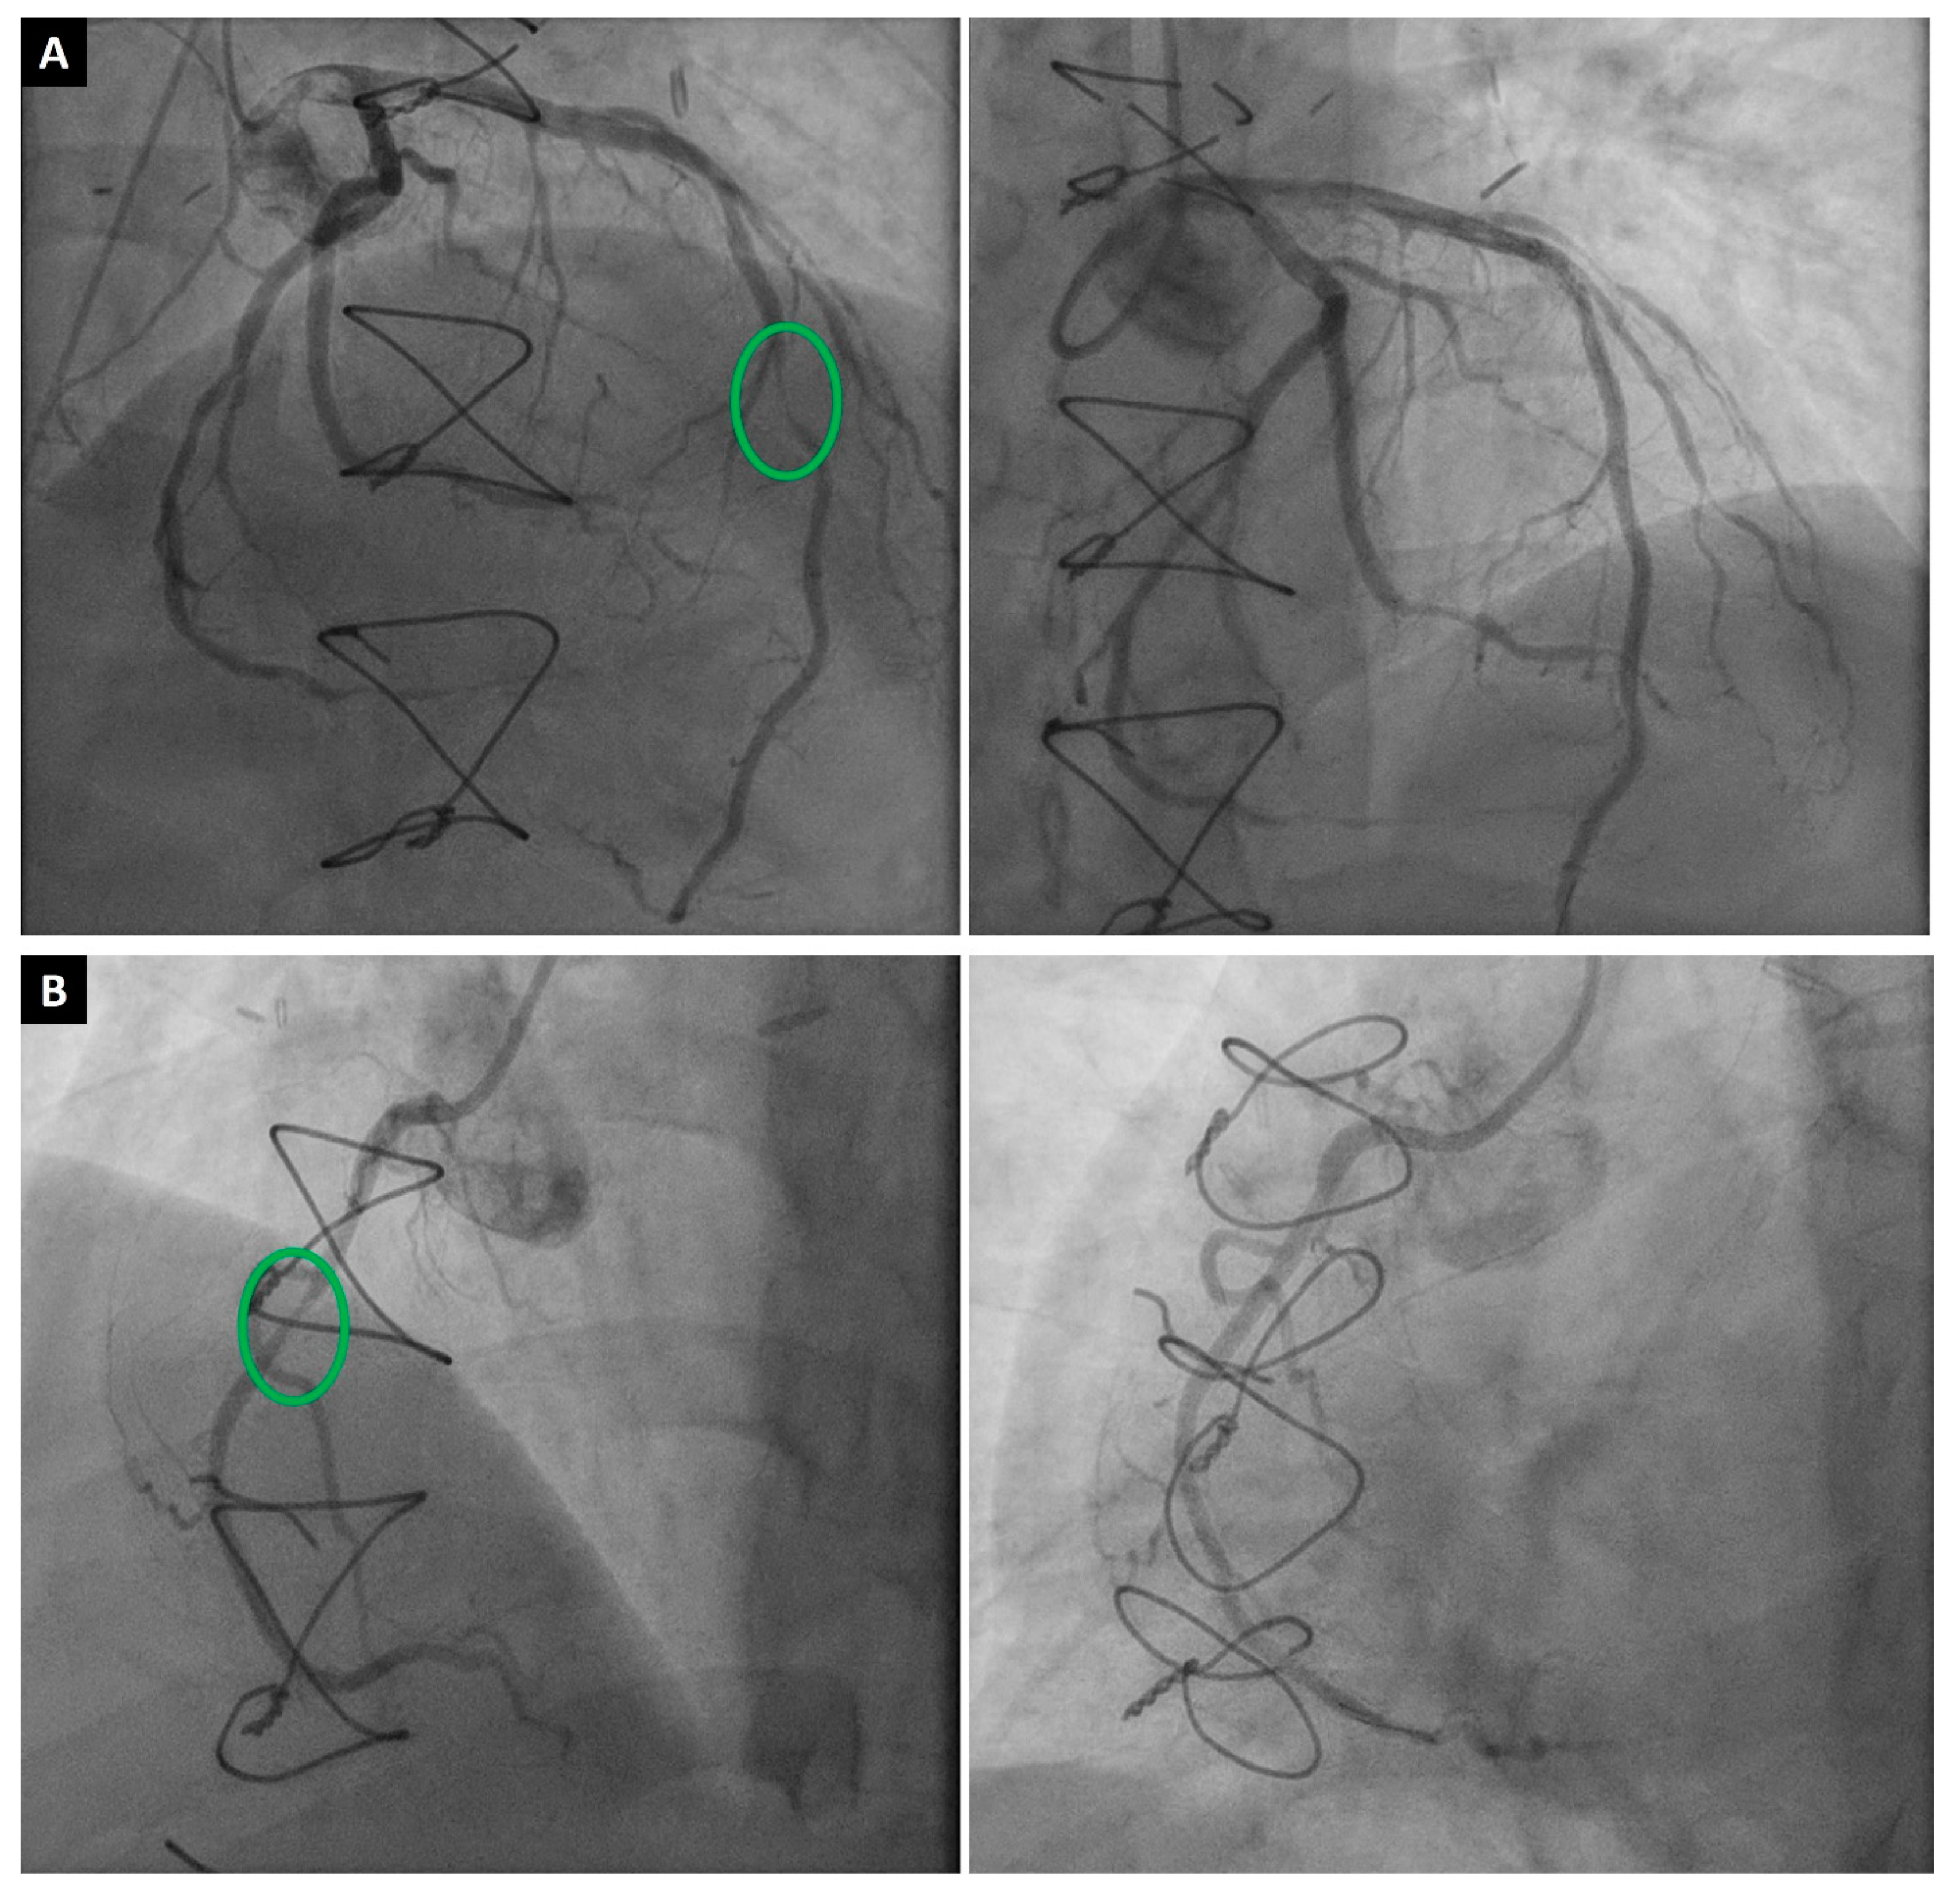

Figure 1.

A 53-year-old male patient who developed severe CAV two years after HTx. (A) Successful intervention of the middle left anterior descending artery (green circle) with one drug-eluting stent (preintervention stenosis was 90%). (B) Successful intervention of the middle right coronary artery (green circle) with one drug-eluting stent (preintervention stenosis was 70%).